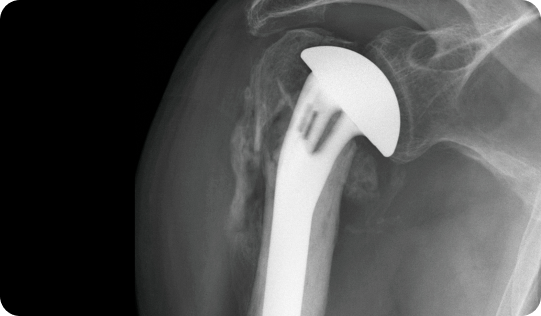

어깨의 움직임과 통증 상태를

면밀히 분석

하여 적절하게

인공관절 수술을 시행합니다.

팔을 들어 올리거나 돌리는 동작에 심한 제한이 있거나 지속적인 통증으로 인해 일상생활에 큰 지장이 있는 경우, 특히나 회전근개 손상 여부에 따라 손상된 관절면을 정밀하게 절제한 뒤 특수 재질의 인공관절로 대체하여 어깨 기능을 회복합니다. 수술 전에는 환자의 근육 상태, 나이, 관절염의 정도 등을 종합적으로 고려해 수술 방식을 결정해야 하며, 회복 과정에서 재활 치료도 매우 중요합니다.